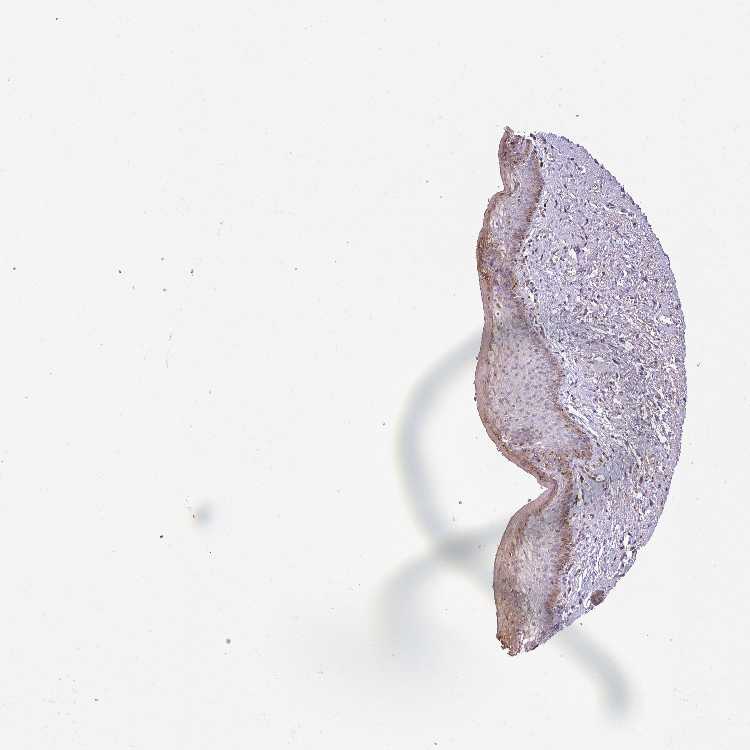

TISSUE PRIMARY DATA VAGINA Show tissue menu

VAGINA - Antibody stainingi

Antibody staining in the annotated cell types in the current human tissue is reported as not detected, low, medium, or high, based on conventional immunohistochemistry profiling in selected tissues. This score is based on the combination of the staining intensity and fraction of stained cells.

Each image is clickable and will lead to virtual microscopy that enables deeper exploration of all samples and also displays staining intensity scores, fraction scores and subcellular localization as well as patient and tissue information for each sample.

Antibody HPA056203Antibody HPA058750

Squamous epithelial cells LowNot detected